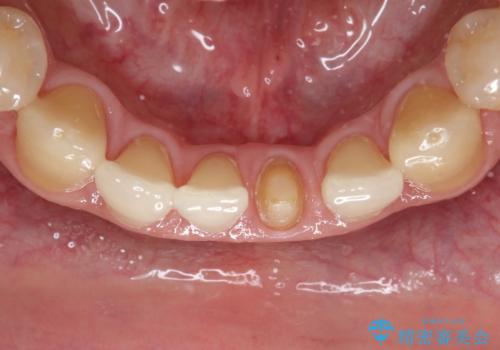

下顎前歯のセラミッククラウン

- 前歯の審美障害を主訴に来院されました。

根管治療を行なったのちオールセラミッククラウン(スタンダード)にて修復治療を行なっております。

歯髄壊死により変色した歯は根管治療が必要となります。